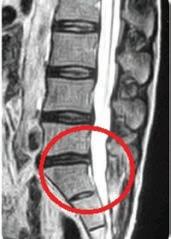

A chiropractic visit can help heal your body naturally and could help you avoid taking medications or having surgery.

We are excited to offer the next level of natural healing, from spinal decompression to laser therapy to nutritional advice. We can offer you choices to getting better, naturally